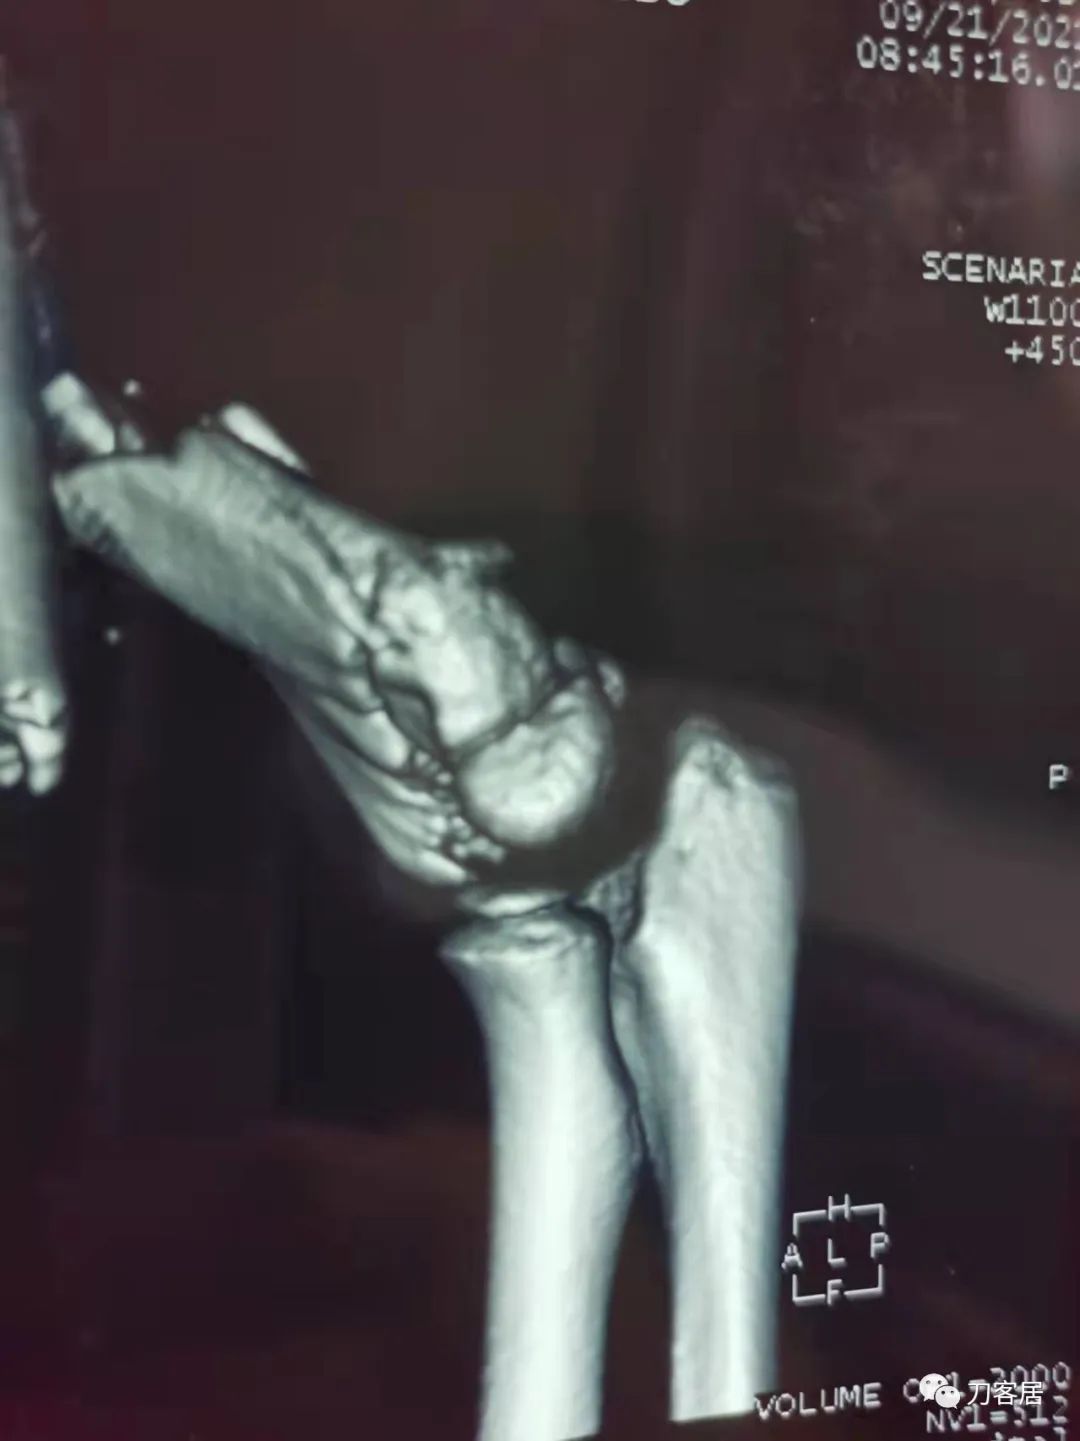

查体:左侧肘关节肿胀明显、疼痛、畸形,局部可见明显青紫瘀斑,左肘关节活动受限,肱骨远端环形压痛(+),局部可及异常活动及骨擦感形成,左上肢末梢桡动脉可触及,左侧腕关节及拇指背伸活动受限,左侧虎口区感觉麻木。辅助检查:自带X线及CT片示:左肱骨髁间粉碎性骨折。

入院诊断:1. 左肱骨髁间粉碎性骨折;2.左肱骨远端骨骺损伤;3. 左桡神经损伤。

20210921当地县医院CT01

20210921当地县医院CT02